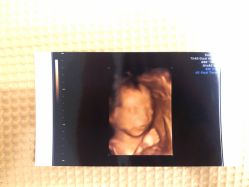

Niki 上传于 19-11-19 | 报错

• -北京俪婴妇产医院(朝阳大悦城店)

相册